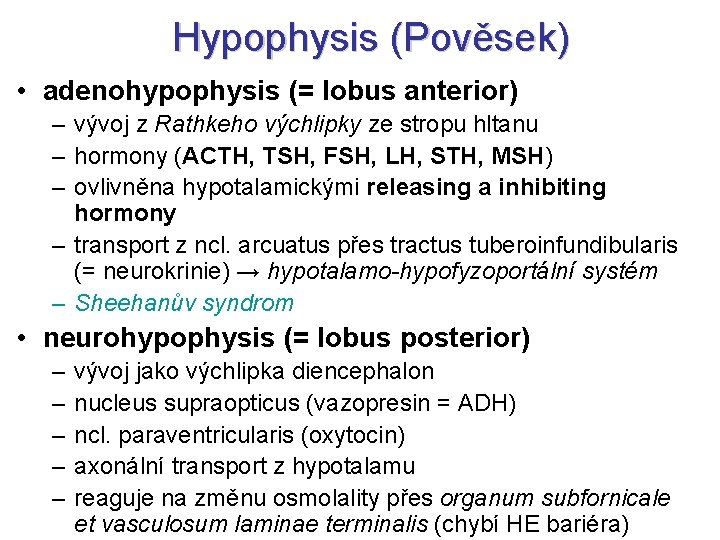

Hypophysis (Pověsek) • adenohypophysis (= lobus anterior) – vývoj z Rathkeho výchlipky ze stropu hltanu – hormony (ACTH, TSH, FSH, LH, STH, MSH) – ovlivněna hypotalamickými releasing a inhibiting hormony – transport z ncl. arcuatus přes tractus tuberoinfundibularis (= neurokrinie) → hypotalamo-hypofyzoportální systém – Sheehanův syndrom • neurohypophysis (= lobus posterior) – – – vývoj jako výchlipka diencephalon nucleus supraopticus (vazopresin = ADH) ncl. paraventricularis (oxytocin) axonální transport z hypotalamu reaguje na změnu osmolality přes organum subfornicale et vasculosum laminae terminalis (chybí HE bariéra)